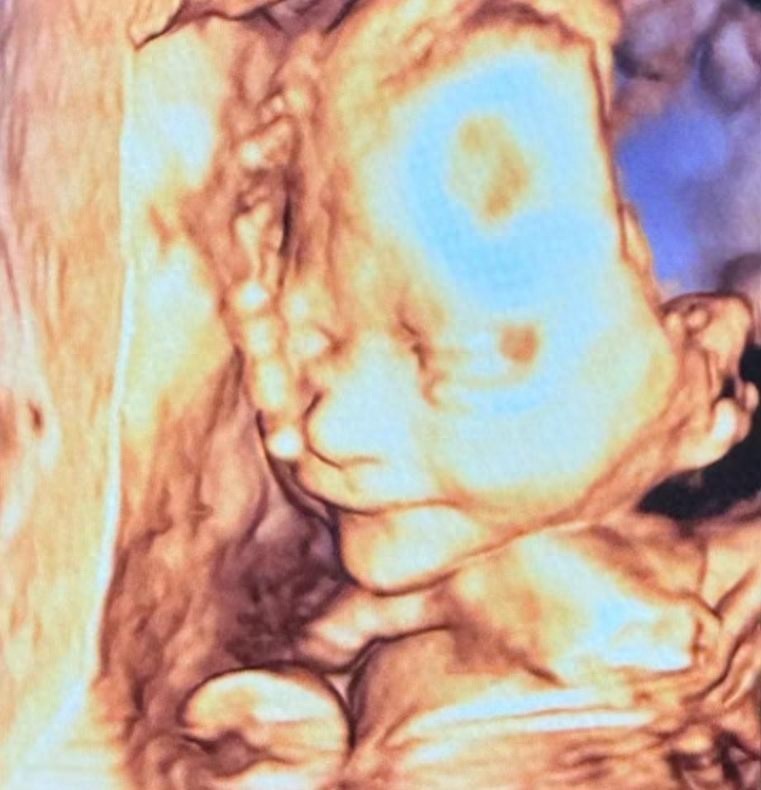

时间倒回三天前,包文婧在社交账号甩出九宫格孕期PLOG,配文“初次见面!新鲜的面条子~“让吃瓜群众集体懵圈。点开大图才发现,这位准妈妈直接把孕晚期日常摊开给网友看:母婴店选购婴儿床时认真比划尺寸,产检路上和老公在车里玩起嘟嘴自拍,甚至大方展示八个月圆润孕肚。更惊喜的是,五岁女儿包饺子写给爸爸的童诗意外曝光,歪歪扭扭的“爸爸是超人“字迹萌化众人。原来夫妻俩特意选在孕晚期稳定期公开消息,给足粉丝们惊喜大礼包。